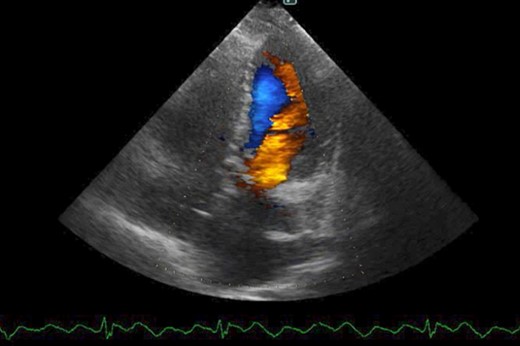

The patient had an uneventful postoperative course during her hospital stay. Echocardiography on postoperative Day 8 showed an EF of 64%, trivial MR, a mean PAP of 18 mmHg, and no shunt flow (Fig. 4). Therefore, the patient was discharged on the 19th day after surgery. The patient is doing very well 7 months after surgery.

Postoperative cardio echography showing an EF of 64%, trivial MR, mean PAP of 18 mmHg, and no shunt flow.